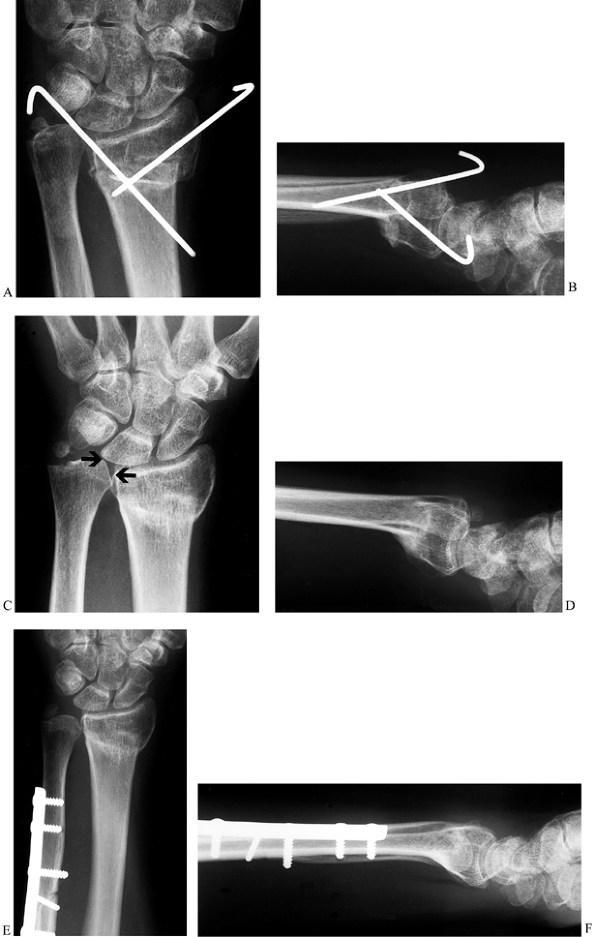

![]() |

Figure 43.10. Ulnar impaction syndrome. Posteroanterior (A) and lateral (B) radiographs showing attempted K-wire fixation of a radius fracture. This resulted in a malunion of the radius (C,D) and ulnar impaction syndrome from the ulnar positive variance (arrows, C), and the patient was referred for further treatment. An ulnar shortening osteotomy was performed (E,F),

combined with arthroscopic debridement of a TFCC tear. The stable fibrous nonunion at the base of the ulnar styloid was left alone. The patient improved significantly and was pain-free at last follow-up. |